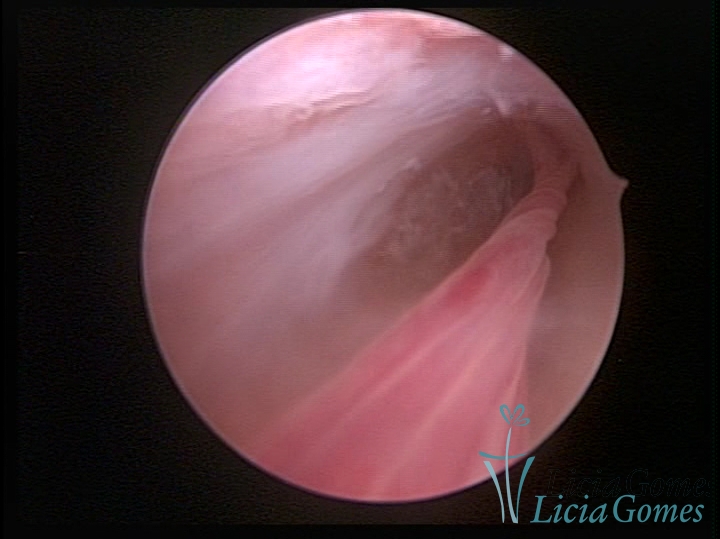

ENDOCERVICAL POLYPS

Benign tumors resulting from the reactive focal proliferation to inflammatory processes or hyperestrogenism situations, which may be sessile (with a large implantation) or stalked.